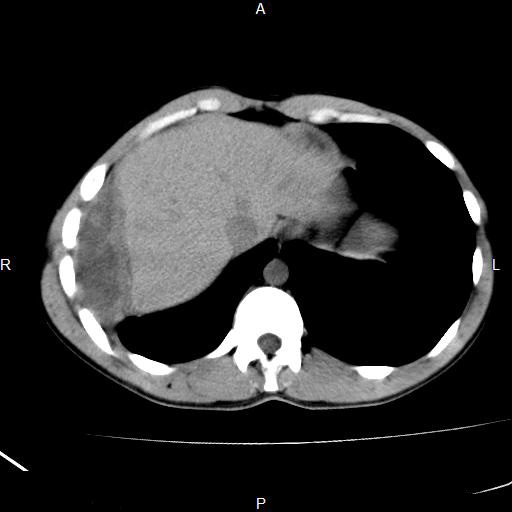

Tràn mủ màng phổi xuyên qua thành ngực (Empyema Necessitans)